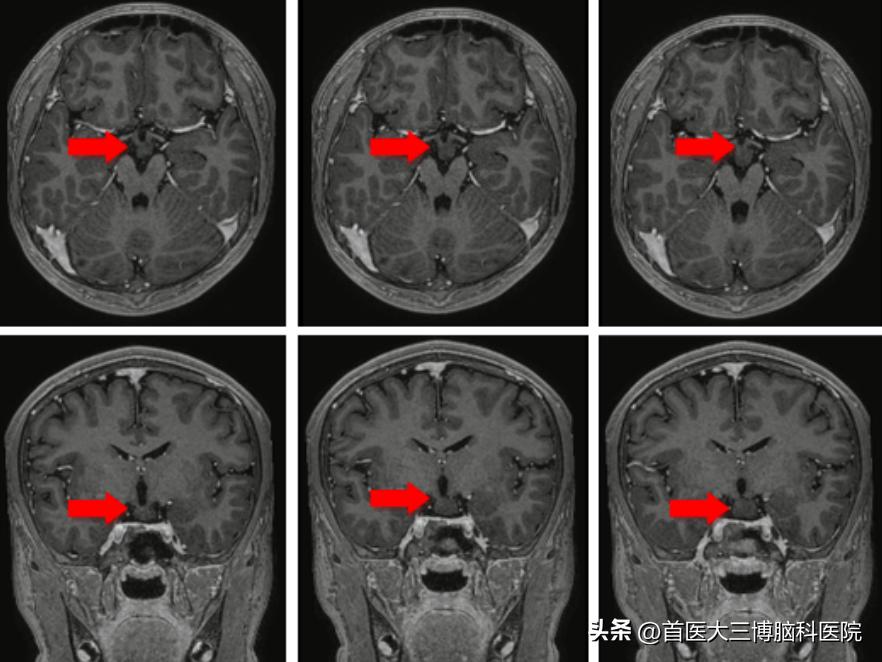

术前头部核磁共振,箭头所示为病变位置

下丘脑错构瘤对于瘤蒂的处理非常关键,处理好瘤蒂才能保证术后的效果。患者三维的头部核磁共振发现病变形态特殊,仅有两个很细的瘤蒂从两侧与脑组织相连,瘤蒂直径最细的地方约1mm,最粗的地方也不超过2mm;如何将直径为0.8mm的电极精准的穿过瘤蒂,成为手术的主要难点,如果有任何哪怕0.5mm的偏差就有可能使电极位置偏移而监测不到异常的放电也无法通过毁损起到彻底阻断放电传导的效果。手术计划最终设计了两根电极,分别沿两侧的瘤蒂长轴穿过,保证对瘤蒂的彻底处理。在成功“消灭”了患者颅内的错构瘤后,将电极安全取出,既保障癫痫灶毁损、又保护了手术的安全性,解决了小文多年癫痫发作的问题。